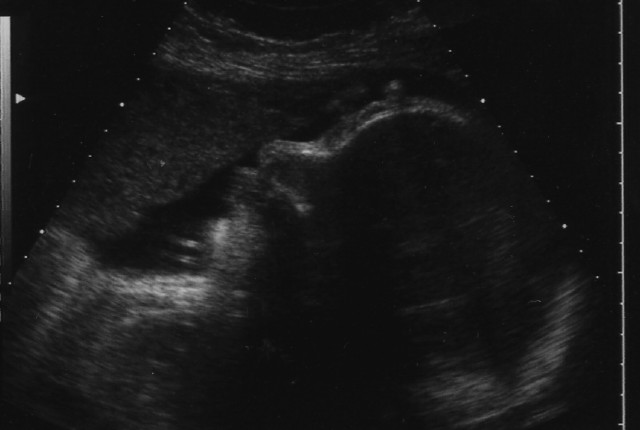

Une dernière petite échographie de contrôle pour redécouvrir bébé sous son meilleur profil.

On ne s'en lasse pas !